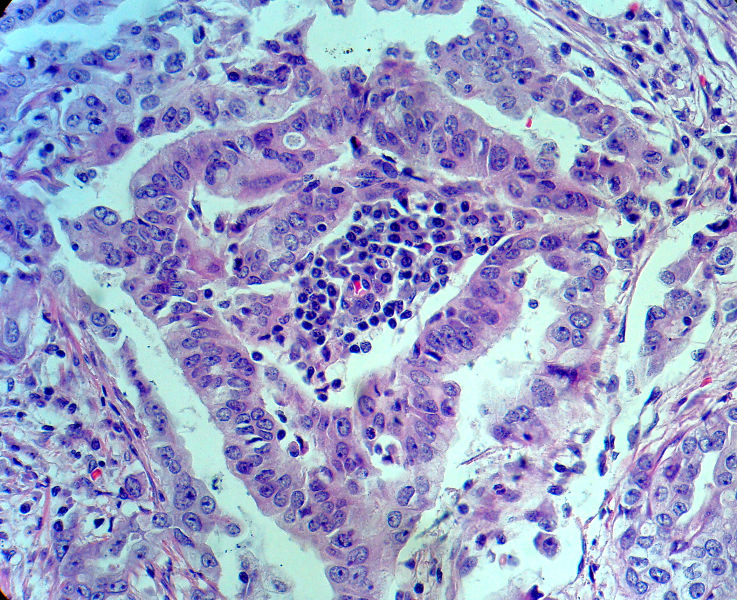

男,82岁,小肠穿孔紧急手术。

大体,小肠一段,长约60厘米,与粘膜面可见三个溃疡型肿物,肠系膜淋巴结肿大。

肿瘤呈巢片状分布,细胞大小相对一致,胞浆丰富,胞核呈细颗粒状,可见小核仁,血管较丰富,考虑神经内分泌肿瘤,加做免疫组化(Ki67、Syn、NSE、CgA、CD56)分级。

神经内分泌肿瘤,加做免疫组化(CKp、Ki67、Syn、NSE、CgA、CD56)分级。